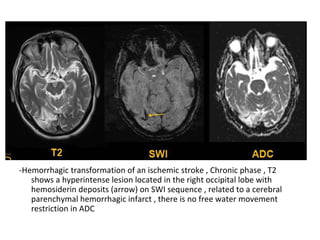

9-Hemorrhage :

-Hemorrhagic transformation is a little variably

used and collectively refers to two different

processes which have different incidence ,

appearance and prognostic implications ,

these are :

a) Petechial hemorrhage

b) Intracerebral hematoma